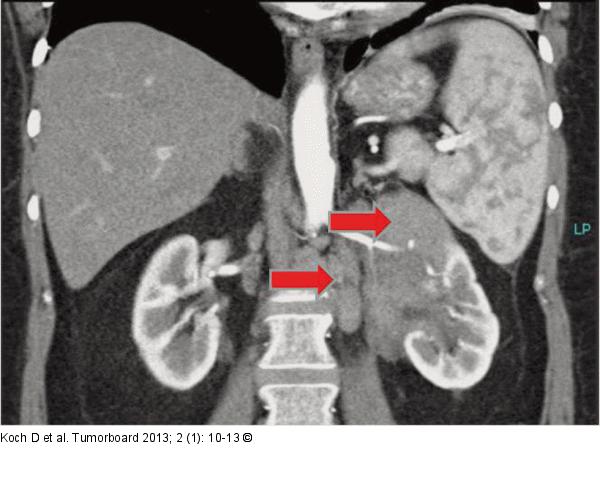

Abbildung 1: Lymphom Raumforderung der li. Niere (oberer Pfeil) und ein paraaortales Lymphom (unterer Pfeil) |

Raumforderung der li. Niere (oberer Pfeil) und ein paraaortales Lymphom (unterer Pfeil) |